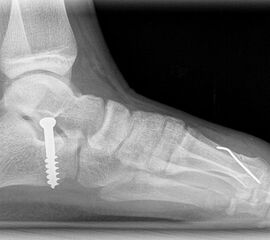

Röntgen

Standard ist die belastete Röntgenaufnahme des Fußes dorso-plantar und seitlich. Günstig ist eine Röhrenkippung von 10°-20°, um die Gelenke der Lisfranc-Linie einsehen zu können.

Ergänzend kann eine Schrägaufnahme hilfreich sein. Bei Metatarsalgien oder Pathologien der Sesambeine liefert die Sprinteraufnahme zusätzliche Informationen. Bei einer Pes planovalgus Fehlstellung wird ergänzend ein Saltzman view durchgeführt.

Bezüglich der Operationstechniken wird von früher häufig durchgeführten alleinigen Weich­teileingriffen am Großzehengrundgelenk aufgrund hoher Rezidivraten abgeraten 15. Die Operation nach Mc Bride mit lateralem Release, Exzision des lateralen Sesambeins, Abtragen der Pseudoexostose, Sehnenetransfer des M. adductor hallucis und mediale Kapselraffung zeigte unbefriedigende Mittel- und Langzeitergebnisse 16. Die Cerclage fibreux (mediale Kapselraffung) und das laterale Kapselrelease wird heute in Kombination mit einem knöchernen Eingriff angewendet. Bezüglich des Einsatzes von minimalinvasiven Operations­techniken vor Wachstumsabschluss liegen bisher keine Daten vor. Alle Osteotomien lassen sich nach Bedarf miteinander kombinieren. Es ist darauf zu achten, dass Osteotomien keine offenen Wachstumsfugen verletzen.

• Medial zuklappende Grundphalanxosteotomie nach Akin 17

• Subcapitale distale Chevron Osteotomie nach Austin 18

• medial aufklappende Cuneiforme I Osteotomie 1522

• Nach Schluss der Wachstumsfugen: TMT I Arthrodese nach Lapidus 2425